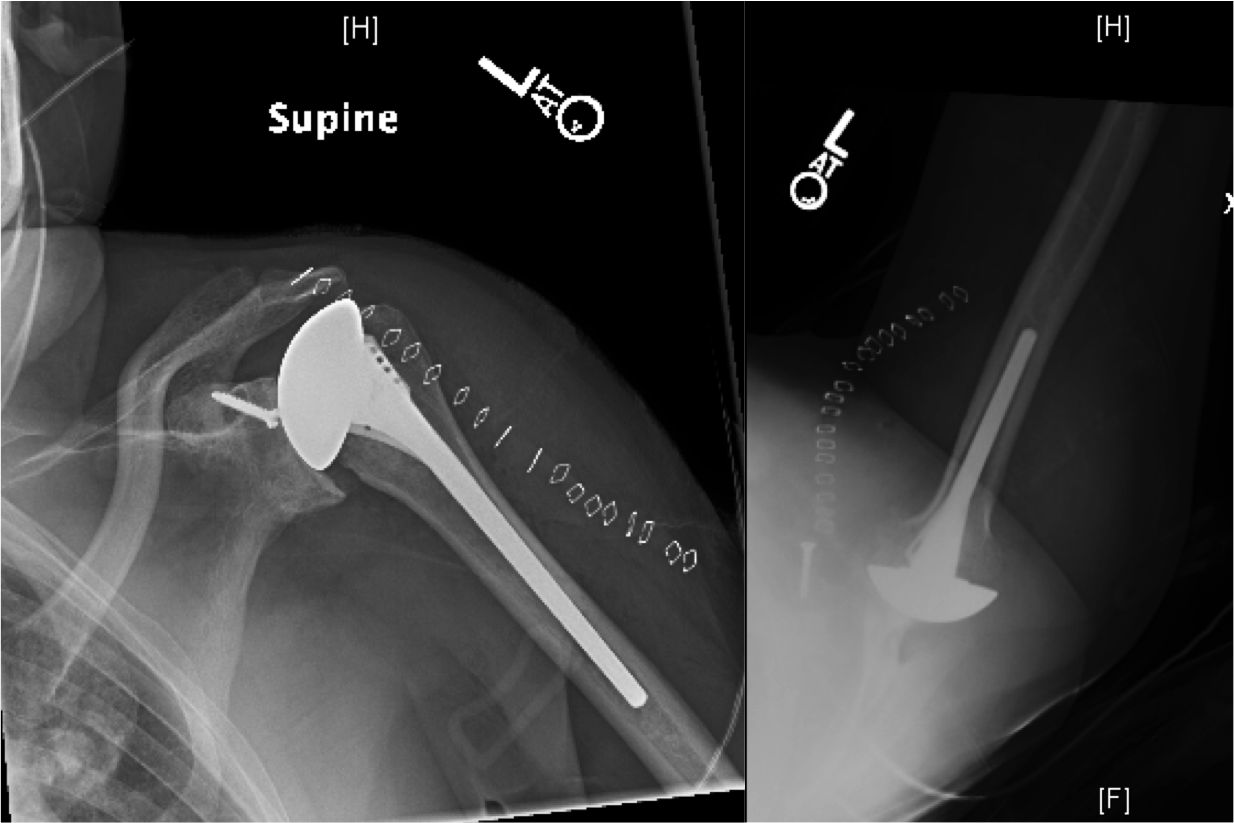

Reverse Total Shoulder Replacement Florida Orthopaedic Institute Rotator Cuff Arthropathy Shoulder Icd 10 the most common indications for shoulder arthroplasty are pain from shoulder arthritis with a loss of function that is unresponsive to. Bilateral rotator cuff arthropathy of. M75.122 complete rotator cuff tear. m12.811 is a billable diagnosis code used to specify a medical diagnosis of other specific arthropathies, not elsewhere classified,. m75.121 is a billable diagnosis code used. Rotator Cuff Arthropathy Shoulder Icd 10.

Rotator Cuff Tear Arthropathy Pathophysiology, Imaging Characteristics Rotator Cuff Arthropathy Shoulder Icd 10 rotator cuff arthropathy is a specific pattern of shoulder degenerative joint disease that results from a rotator cuff tear leading to. the most common indications for shoulder arthroplasty are pain from shoulder arthritis with a loss of function that is unresponsive to. disabling cuff tear arthropathy (cta) is commonly managed with reverse shoulder arthroplasty (rsa). m25.811. Rotator Cuff Arthropathy Shoulder Icd 10.